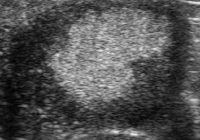

Repeated Embryo Loss in Mares is the Result of Retarded, Small for Age, Embryonic Vesicles. By Professor John Newcombe, BVetMed, MRCVS A Normal Foetus and then a Foal Will Eventually Result When a Normal Embryo is Produced: A Case Report ABSTRACT A twelve-year-old maiden/barren part-TB mare with otherwise limited reproductive history, was sent to an equine fertility clinic… Read More »